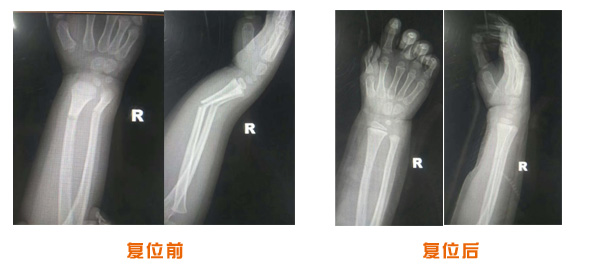

復(fù)位前后對(duì)比

肘關(guān)節(jié)脫位骨折治療前后對(duì)比